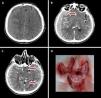

Dural metastases originating from prostate cancer are exceedingly uncommon and may clinically imitate a subdural hematoma. Additionally, head computed tomography scan findings can be mistaken for meningioma or subdural hematoma. We present a 75-year-old male patient with dural metastasis as a first presenting sign of prostate cancer, misdiagnosed as a bilateral subdural hematoma on initial non-contrast brain CT scan. Also, a review of literature is presented. We found 12 cases of dural metastasis of prostate cancer mimicking subdural hematoma described in the literature, and unlike in our case, prostate cancer was already diagnosed.